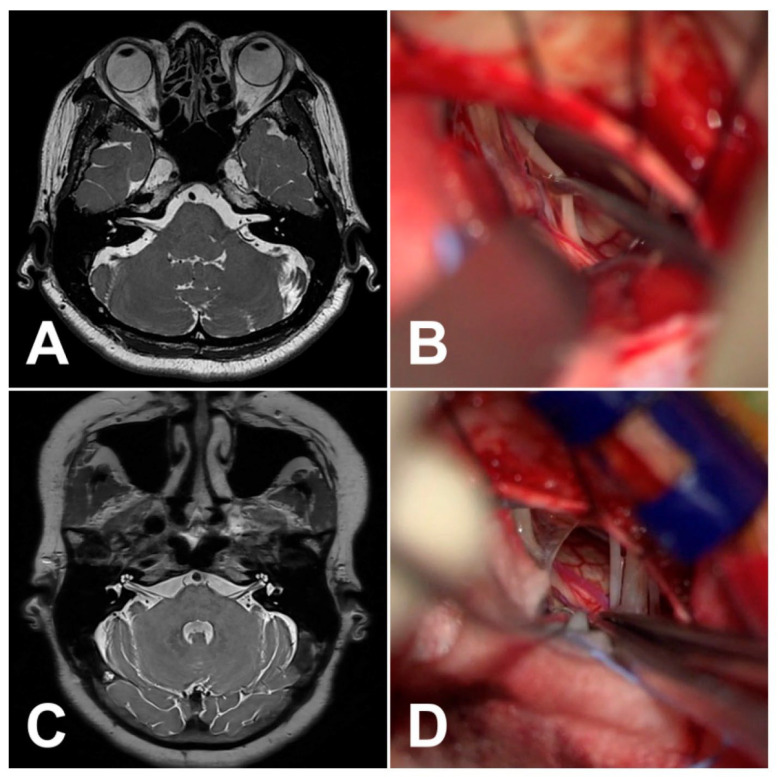

面肌痉挛(HFS)是整形外科医生需要了解的一个重要情况,因为它会显著影响患者的生活质量,并使美容和重建手术复杂化。磁共振成像(MRI)在诊断HFS、评估神经血管关系和计划治疗方面变得至关重要。MRI横断面扫描常显示面神经附着点下桥向上移位,提示HFS的神经血管受压(NVC)。对于神经外科医生来说,重要的解剖学特征包括小脑萎缩和“小后窝”,这可以通过缩小液体空间导致HFS。HFS患者的后窝通常更充血,解剖平面可能加剧椎基底动脉外侧偏曲。此外,评估乙状窦优势和其他解剖变异对手术计划至关重要,特别是在动脉高压可能影响髓质压迫的情况下。

Hemifacial spasm (HFS) is an important condition for plastic surgeons to understand, as it significantly affects patients' quality of life and can complicate aesthetic and reconstructive procedures. Magnetic resonance imaging (MRI) has become vital in diagnosing HFS, assessing neurovascular relationships, and planning treatment. Transverse MRI scans often show an upward displacement of the inferior pons at the facial nerve attachment point, signaling neurovascular compression (NVC) in HFS. Important anatomical features for neurosurgeons include cerebellar atrophy and a "small posterior fossa," which can lead to HFS by narrowing fluid spaces. The posterior fossa is often more congested in HFS patients, and anatomical flatness may exacerbate lateral deviation of the vertebrobasilar arteries. Additionally, evaluating sigmoid sinus dominance and other anatomical variations is crucial for surgical planning, particularly in cases of arterial hypertension that may affect medullary compression.